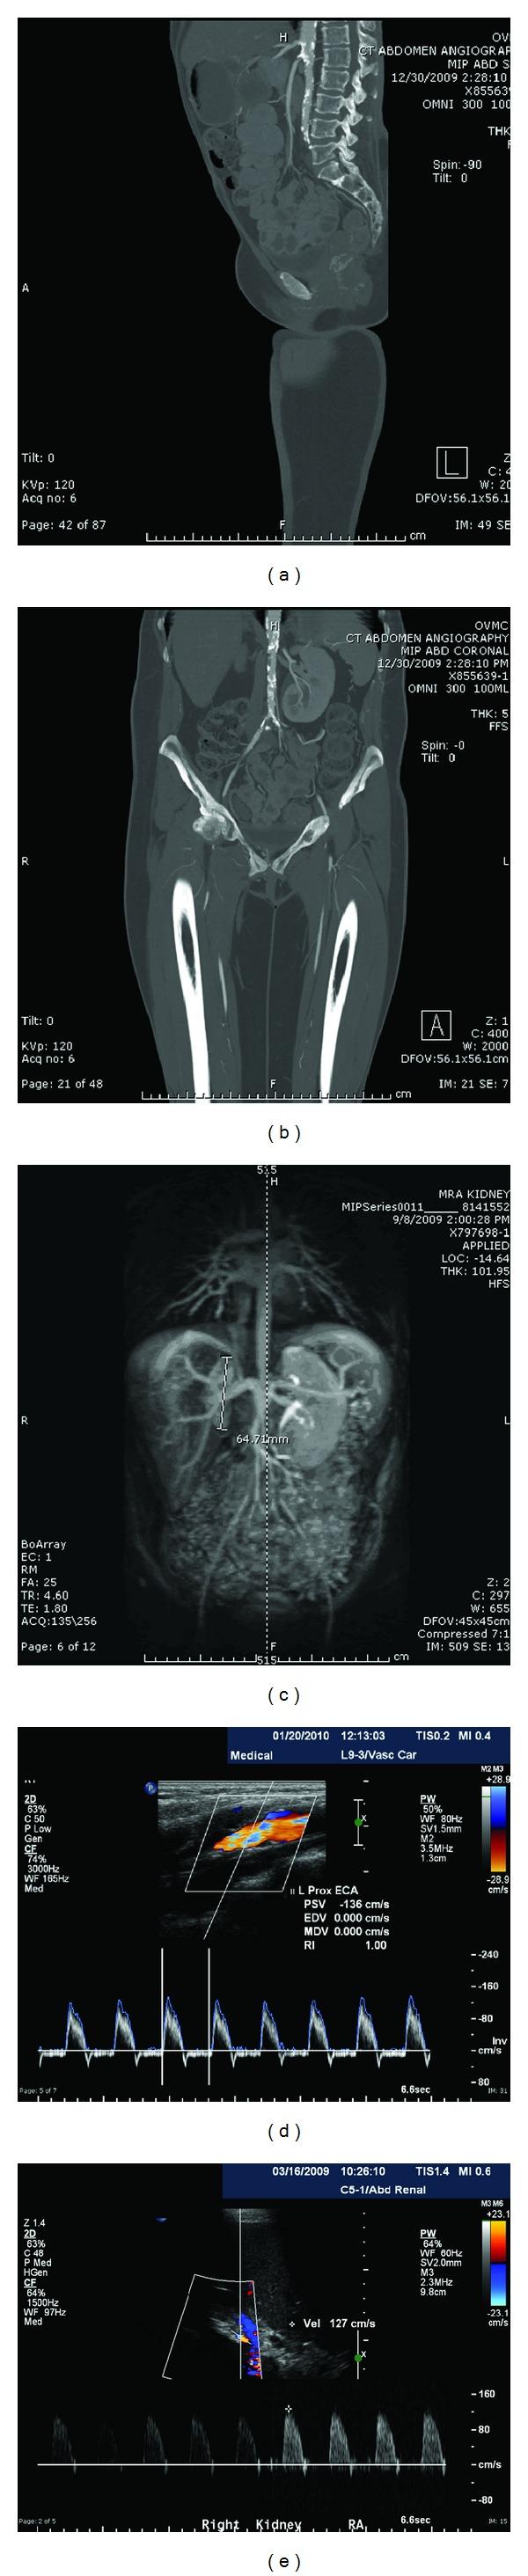

Three Presentations of Takayasu's Arteritis in Hispanic Patients.

Takayasu's arteritis (TA) is a medium and large vessel vasculitis, defined as a nonspecific aortitis that usually involves the aorta and its branches Kobayashi and Numano (2002). Its etiology remains unclear, and its complications are diverse and severe, including stenosis of the thoracic and abdominal aorta, aortic valve damage and regurgitation, and stenosis of the branches of the aorta. Carotid stenosis, coronary artery aneurysms, and renal artery stenosis resulting in renovascular hypertension are also reported sequellae of TA Kobayashi and Numano (2002). The disease was first described in Japan, but has also been diagnosed in India and Mexico Johnston (2002). Its incidence in the United States has been quoted as 2.6 patients per 1,000,000 people/year Johnston (2002). In Japan, its incidence is 3.6 patients per 1,000,000 patients/year and prevalence is 7.85 patients per 100,000 per year Morita et al. (1996). The natural history of this disease, which is commonly present in Asian populations, has only recently been studied in Hispanic patients despite the notable incidence and prevalence of TA in Mexican, South American, and Indian populations (Johnston 2002, Gamarra et al. 2010 ). We present three cases of Hispanic patients who presented with TA at Olive-View-UCLA Medical Center (OVMC). We review their clinical and radiographic presentations. Finally, we review the literature to compare the clinical features of our three patients with data regarding the presentation of TA in more traditional Asian populations.